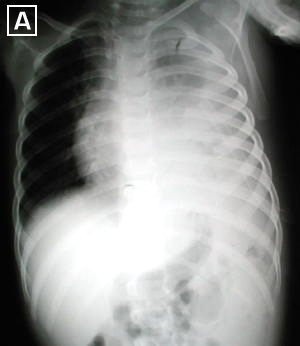

Rx. Tórax PA. (A). posterior a la insercion del tubo de tórax para drenaje pleural. radiopacidad difusa del hemitórax izquierdo, con colapso parcial pulmonar, desviación mediastinal hacia la derecha. Por proceso neumonico con derrame pleural.